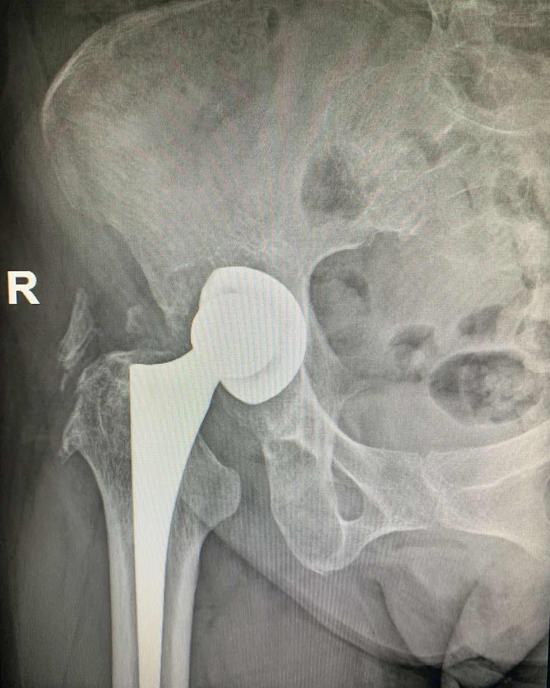

x光片骨盆,女性骨盆x光片

术前骨盆x线平片

骨盆x光片分析(站立位),看片不求人

16,power角:骨盆正位片,过两侧髂前上棘做一水平线,再做股骨颈骨折的

术前x光片